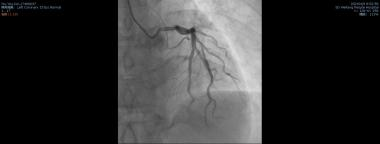

患者的一系列结果与症状都指向急性心肌梗死,立即在北辰院区行冠状动脉造影术,冠脉造影结果: